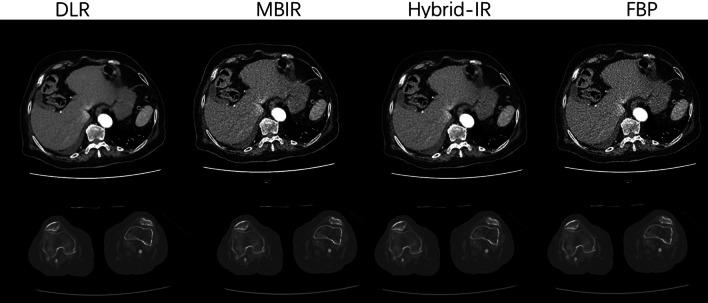

To evaluate the image quality of lower extremity computed tomography angiography (CTA) with deep learning-based reconstruction (DLR) compared to model-based iterative reconstruction (MBIR), hybrid-iterative reconstruction (HIR), and filtered back projection (FBP).

Fifty patients (38 males, average age 59.8 ± 19.2 years) who underwent lower extremity CTA between January and May 2021 were included. Images were reconstructed with DLR, MBIR, HIR, and FBP. The standard deviation (SD), contrast-to-noise ratio (CNR), signal-to-noise ratio (SNR), noise power spectrum (NPS) curves, and the blur effect, were calculated. The subjective image quality was independently evaluated by two radiologists. The diagnostic accuracy of DLR, MBIR, HIR, and FBP reconstruction algorithms was calculated.

The CNR and SNR were significantly higher in DLR images than in the other three reconstruction algorithms, and the SD was significantly lower in DLR images of the soft tissues. The noise magnitude was the lowest with DLR. The NPS average spatial frequency (f) values were higher using DLR than HIR. For blur effect evaluation, DLR and FBP were similar for soft tissues and the popliteal artery, which was better than HIR and worse than MBIR. In the aorta and femoral arteries, the blur effect of DLR was worse than MBIR and FBP and better than HIR. The subjective image quality score of DLR was the highest. The sensitivity and specificity of the lower extremity CTA with DLR were the highest in the four reconstruction algorithms with 98.4% and 97.2%, respectively.

Compared to the other three reconstruction algorithms, DLR showed better objective and subjective image quality. The blur effect of the DLR was better than that of the HIR. The diagnostic accuracy of lower extremity CTA with DLR was the best among the four reconstruction algorithms.